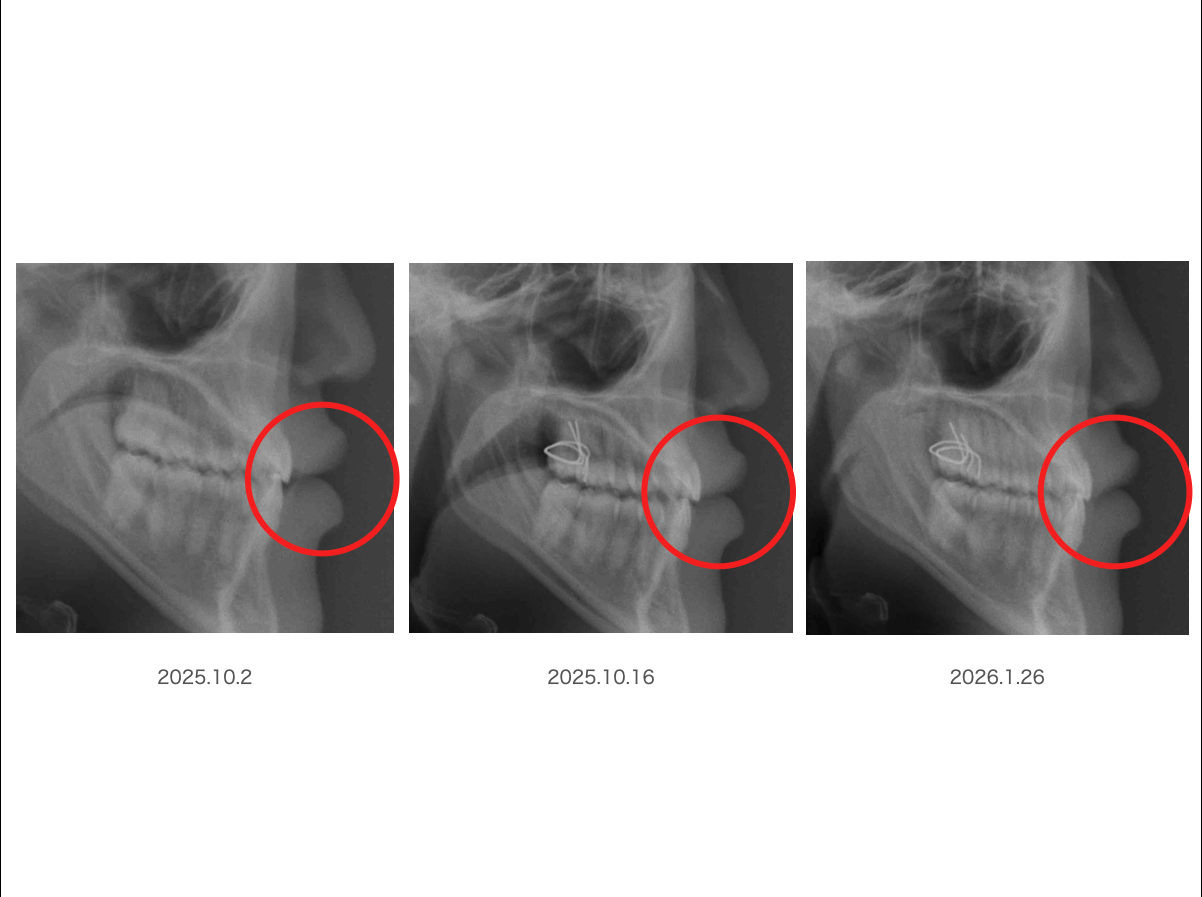

ではここはどうですか?

わかりますか?

では赤丸で囲みますよ〜

よ〜く見比べてくださいね

ここは分かりにくいかもしれませんが、左のレントゲンと右のレントゲンでは唇の厚さが違うことが見えますか?

前歯との距離を見てみると分かりやすいかもしれませんが、左のレントゲンでは「口を閉じる」事が起きていますが、社会人になると口ポカンは恥ずかしいと学ぶので脳はいつも口を閉じた状態をキープしようとするでしょう

これに対して右のレントゲンでは「口唇閉鎖」が起きており、このことはご本人も気づいていないでしょう

だってこれは中枢が勝手にやっていることだからです

この時「口輪筋が無意識に活動している」のです

これは日本歯科大学名誉教授考案のBBという装置を装着しただけです